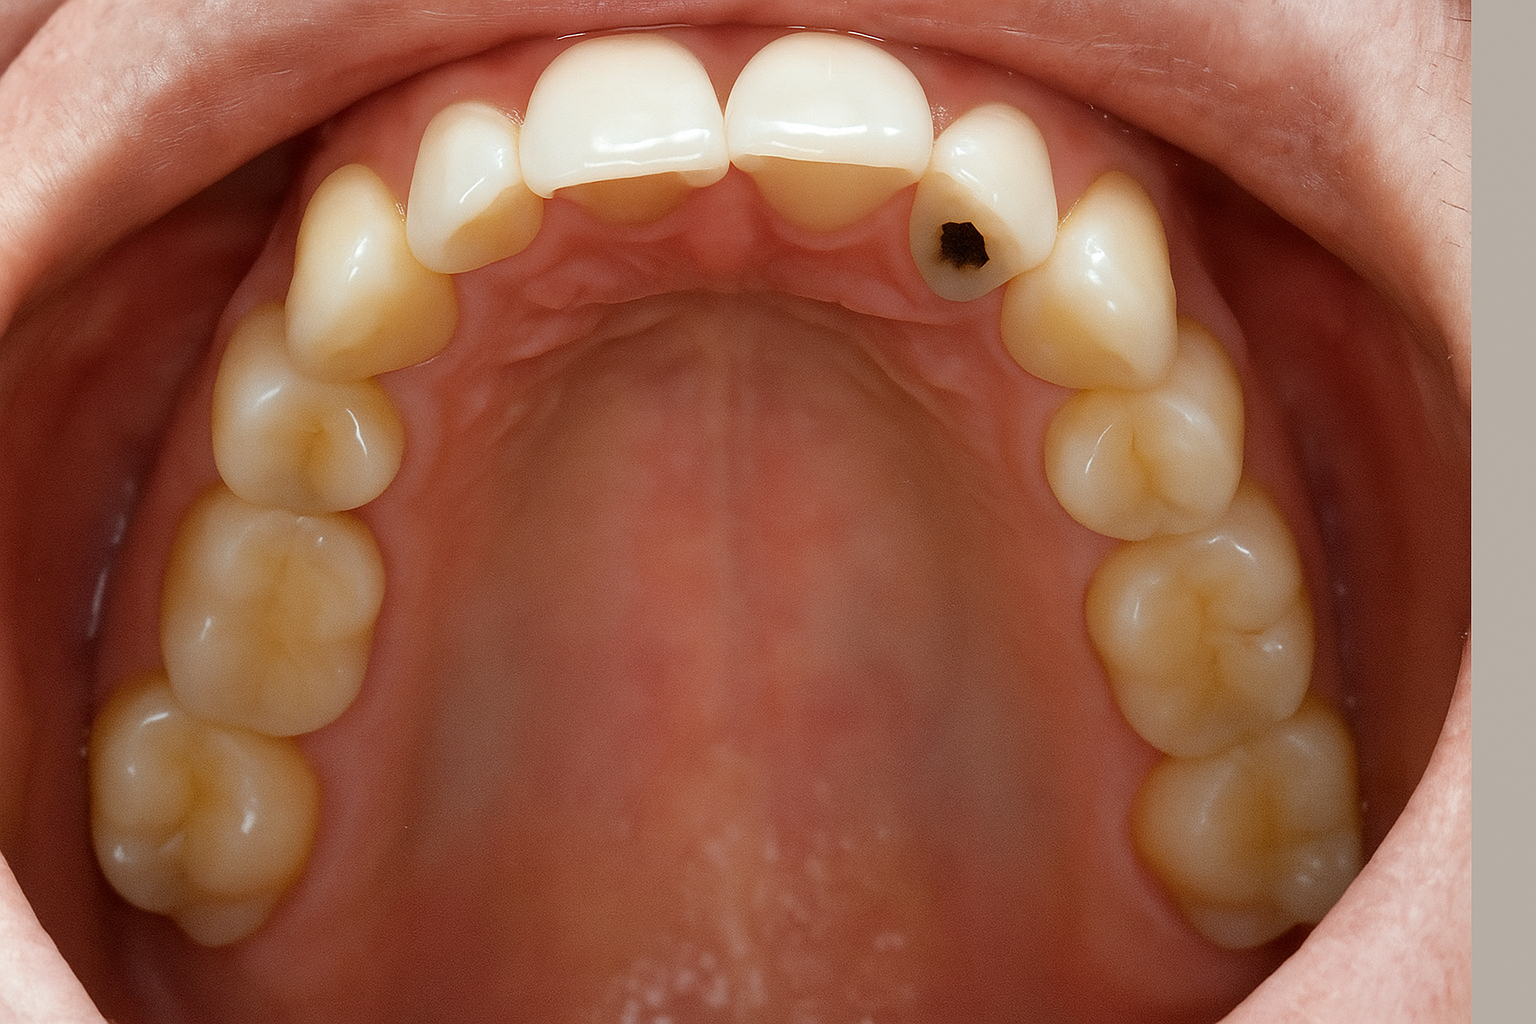

03 Nov Fixing a Cavity on Your Front Tooth: Why Composite Dental Fillings Are the Perfect Choice

A cavity on your front tooth can be both uncomfortable and noticeable, affecting your smile and confidence. Fortunately, composite dental fillings offer a natural-looking, durable solution for restoring your teeth while keeping your smile intact. At Brookside Dental Arts, NJ, Dr. Angra and his experienced...